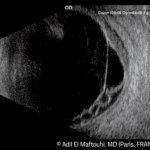

Nový ultrazvukový prístroj Compact Touch ponúka režimy A/B a pachymetriu. Ťaží z novej generácie 15MHz sondy so zvýšeným rozlíšením až o 30 %. Vďaka malým rozmerom sa zmestí do akéhokoľvek pracovného prostredia, dokonca aj do tých najmenších vyšetrovacích miestností. Po pripojení ľahko prepojí namerané údaje s vašimi sieťami DICOM, EMR alebo Wifi.

- nová 15 MHz sonda prináša výnimočnú kvalitu obrazu pre lepšiu a rýchlejšiu diagnostiku,

- kombinuje 3 v jednom 15 MHz B-scan, voliteľná sonda – pachymetria, A-scan.